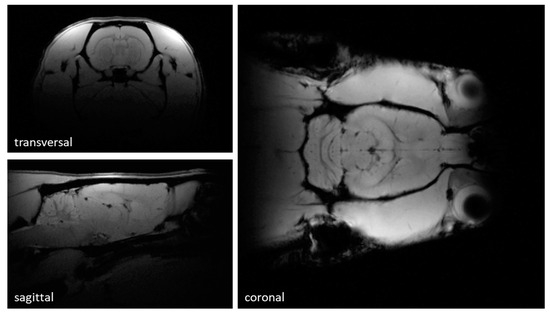

3.3. MR Measurements